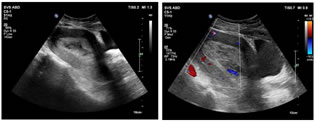

A 40 years old nulliparous premenopausal woman, presented to the gynaecology OPD with a chief complaint of abnormal uterine bleeding and pain in the lower abdomen, predominantly towards left side since an year. The patient had no significant relevant past history or risk factors. The clinical examination of the abdomen revealed no palpable mass. Abdominal ultrasound revealed a solid heterogeneously hypoechoic mass lesion arising from the left ovary, measuring approximately 55x53x50mm and showing moderate colour flow on colour doppler. A moderately enlarged uterus with increase in endometrial thickness was also identified (24 mm). No suspicious abdominal lymphadenopathy was noted. MRI Pelvis showed a single large well defined moderately enhancing, mixed predominantly solid lesion measuring approximately 60x58x53mm (MLXCCXAP) in the left adnexa, which is heterogeneously hypointense on T1W, Isointense with central hypointense areas on T2W, heterogeneously hyperintense with central hypointense areas on T2W/STIR and showing no restricted diffusion on DWI. Uterus appears moderately enlarged with multilobulated heterogenous diffuse moderately enhancing solid areas and non-enhancing cystic areas within the endometrial cavity. No suspicious pelvic lymphadenopathy was noted. Serum CA-125 concentration was elevated,95 U/mL (normal range <35 U/mL). After the positive frozen section pathological examination of the left ovary, the patient underwent a total abdominal hysterectomy, bilateral salpingo-oophorectomy, bilateral pelvic and para-aortic lymphadenectomy, and omentectomy. Pathological findings revealed a well-differentiated endometrioid carcinoma of the left ovary and a well-differentiated endometrioid carcinoma of the endometrium. The patient did not receive any adjuvant chemotherapy or radiotherapy and was suggested for a regular follow-up. Up to the last follow-up visit (April 2021), the patient had no recurrence.

Figure 9: T2 STIR Mixed solid and cystic areas in the endometrial cavity; Figure 10: T2 STIR Mixed predominantly solid lesion involving the left adnexa showing Isointense with central hypointense areas; Figure 11: T1+C showing multilobulated heterogenous diffuse moderately enhancing solid areas and non-enhancing cystic areas in the endometrial cavity; Figure 12: T1+C showing a single large well defined moderately enhancing, mixed predominantly solid lesion involving the left adnexa;